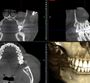

3DCTレントゲン

・CT設備の完備骨の画像を立体的に写し出します。院内で対応できるためお手間をとらせません。

診査・診断

お口の中の型どりとレントゲン撮影を行い、骨の量や質、形を診査します。埋入シミュレーションソフトで位置決めをします。

当院では、低侵襲で安全なガイデッドサージェリ―をお薦めしています。ガイデッドサージェリーとは、CT撮影をして、インプラントを稙立する部位をコンピューターにてシュミレーション。それをもとに、サージカルガイドを作成し、正確な位置にインプラントを稙立することができる技術です。

最近、インプラントの手術時のトラブルが急増しています。

ガイデッドサージェリーを行うことで、確実に手術時のトラブルを回避することが出来ます。

骨格や骨質を

正確に判断骨量や骨質を正確に判断し、インプラント埋入位置を決定。

重大な事故を防ぐ

下歯槽管(下あごの神経)の位置関係や骨形態を把握することで安全に手術を行えます。